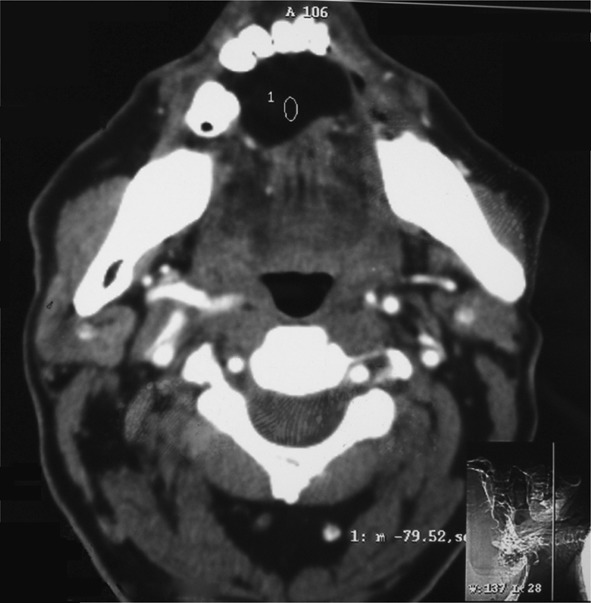

Ultrasonography showed an altered echotexture lesion measuring 3.7 × 2.4 cm in the floor of the mouth without internal vascularity (Fig. 2). Computed tomography scan showed a well defined fat density lesion of 3.7 × 2.5 cm in the floor of the mouth indenting the genioglossus muscle suggestive of dermoid cyst or lipoma (Fig. 3). Fine needle aspiration yielded no fluid and was inconclusive. Based on the above findings, the provisional diagnosis of benign lesions such as lipoma or adenoma was made owing to the nature of the lesion such as size, normal overlying mucosa, nonfluctuant and slow growing nature and a lack of nodal involvement.

Fig. 3.

Computed tomography showing well defined fat density lesion in the floor of mouth

Lipoma has a characteristic radiographic appearance. On computed tomography scan it shows a high density from 83 to 143 Hamsfield units with well or poorly defined margins depending on the capsule [11]. Ultrasonography shows a lesion which is round or elliptical in shape with intact or mostly intact capsule [12]. Most lipomas are hypoechoic with ecogenic lines or spots [11, 12].